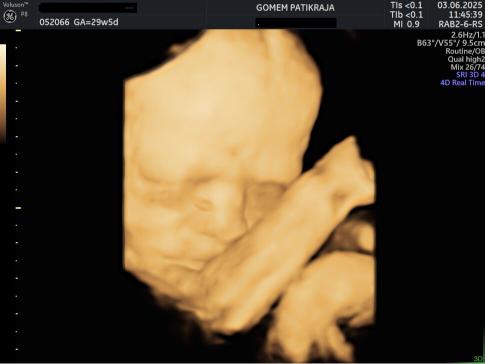

USG Janin 29 Minggu

Informasi Minggu Ke-29

Janin terus menambah cadangan antibodi dari ibu melalui plasenta. Lapisan lemak di bawah kulitnya akan membantunya mengatur suhu tubuh setelah lahir. Denyut jantungnya kini lebih stabil dan kuat.